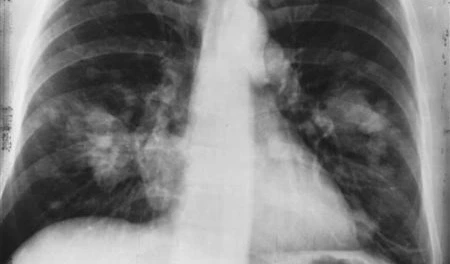

In the retrospective study, clinicians, scientists, and researchers created a machine learning model to see if it could reliably identify patients with non-small cell lung cancer (NSCLC) who were at risk of recurrence after radiation. Machine learning is a type of AI that allows the software to predict outcomes automatically.

Lung cancer is the leading cause

Lung cancer is the major cause of cancer death worldwide, accounting for slightly more than a fifth (21%) of cancer fatalities in the United Kingdom. NSCLC accounts for approximately five-sixths (85 percent) of all lung cancer occurrences, and the disease is often treatable if detected early. In the UK, however, more than a third (36%) of NSCLC patients have a recurrence.

The researchers fed their algorithm with clinical data from 657 NSCLC patients treated at five UK hospitals, as well as data on numerous prognostic markers to better predict a patient's probability of recurrence.

These comprised the patient's age, gender, BMI, smoking status, radiation intensity, and tumor features. The AI model was then utilized by the researchers to define patients as having a low or high risk of recurrence, how long they might experience until recurrence, and overall survival two years after therapy.

The tool was proven to be more accurate than traditional approaches in forecasting outcomes. The findings of the study, which was funded by the Royal Marsden Cancer Charity and the National Institute for Health Research, were published in the journal The Lancet’s eBioMedicine.